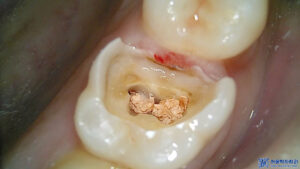

먼저 충치가 매우 깊었던

왼쪽 위 큰 어금니는

충치로 인해 치아가 파절되어 있는

상황이었습니다.

또한 씹는면 주변으로

치석이 쌓여있는 것으로 보아

관리가 잘 안되고 있는것으로

볼 수 있었습니다.

해당 부위는 신경치료를 진행하여

깊은 충치로 인한 치아 내부의

감염을 제거하고 치아의 기능을

회복할 수 있도록 했습니다.

또한 치아 뿌리까지 노출된 상태였고

신경 오염이 많이 된 상태여서

자연치아를 살리기에 많은 노력이

필요한 상황이었습니다.

이렇게 신경치료를 진행하며

먼저 충치 제거 후,

감염된 치아 내부를

철저히 청소하고 소독하였습니다.

이후, 치아의 신경을 제거하고

깨끗하게 정리한 뒤,

빈 공간을 충전재로 채워

치아를 밀봉했습니다.